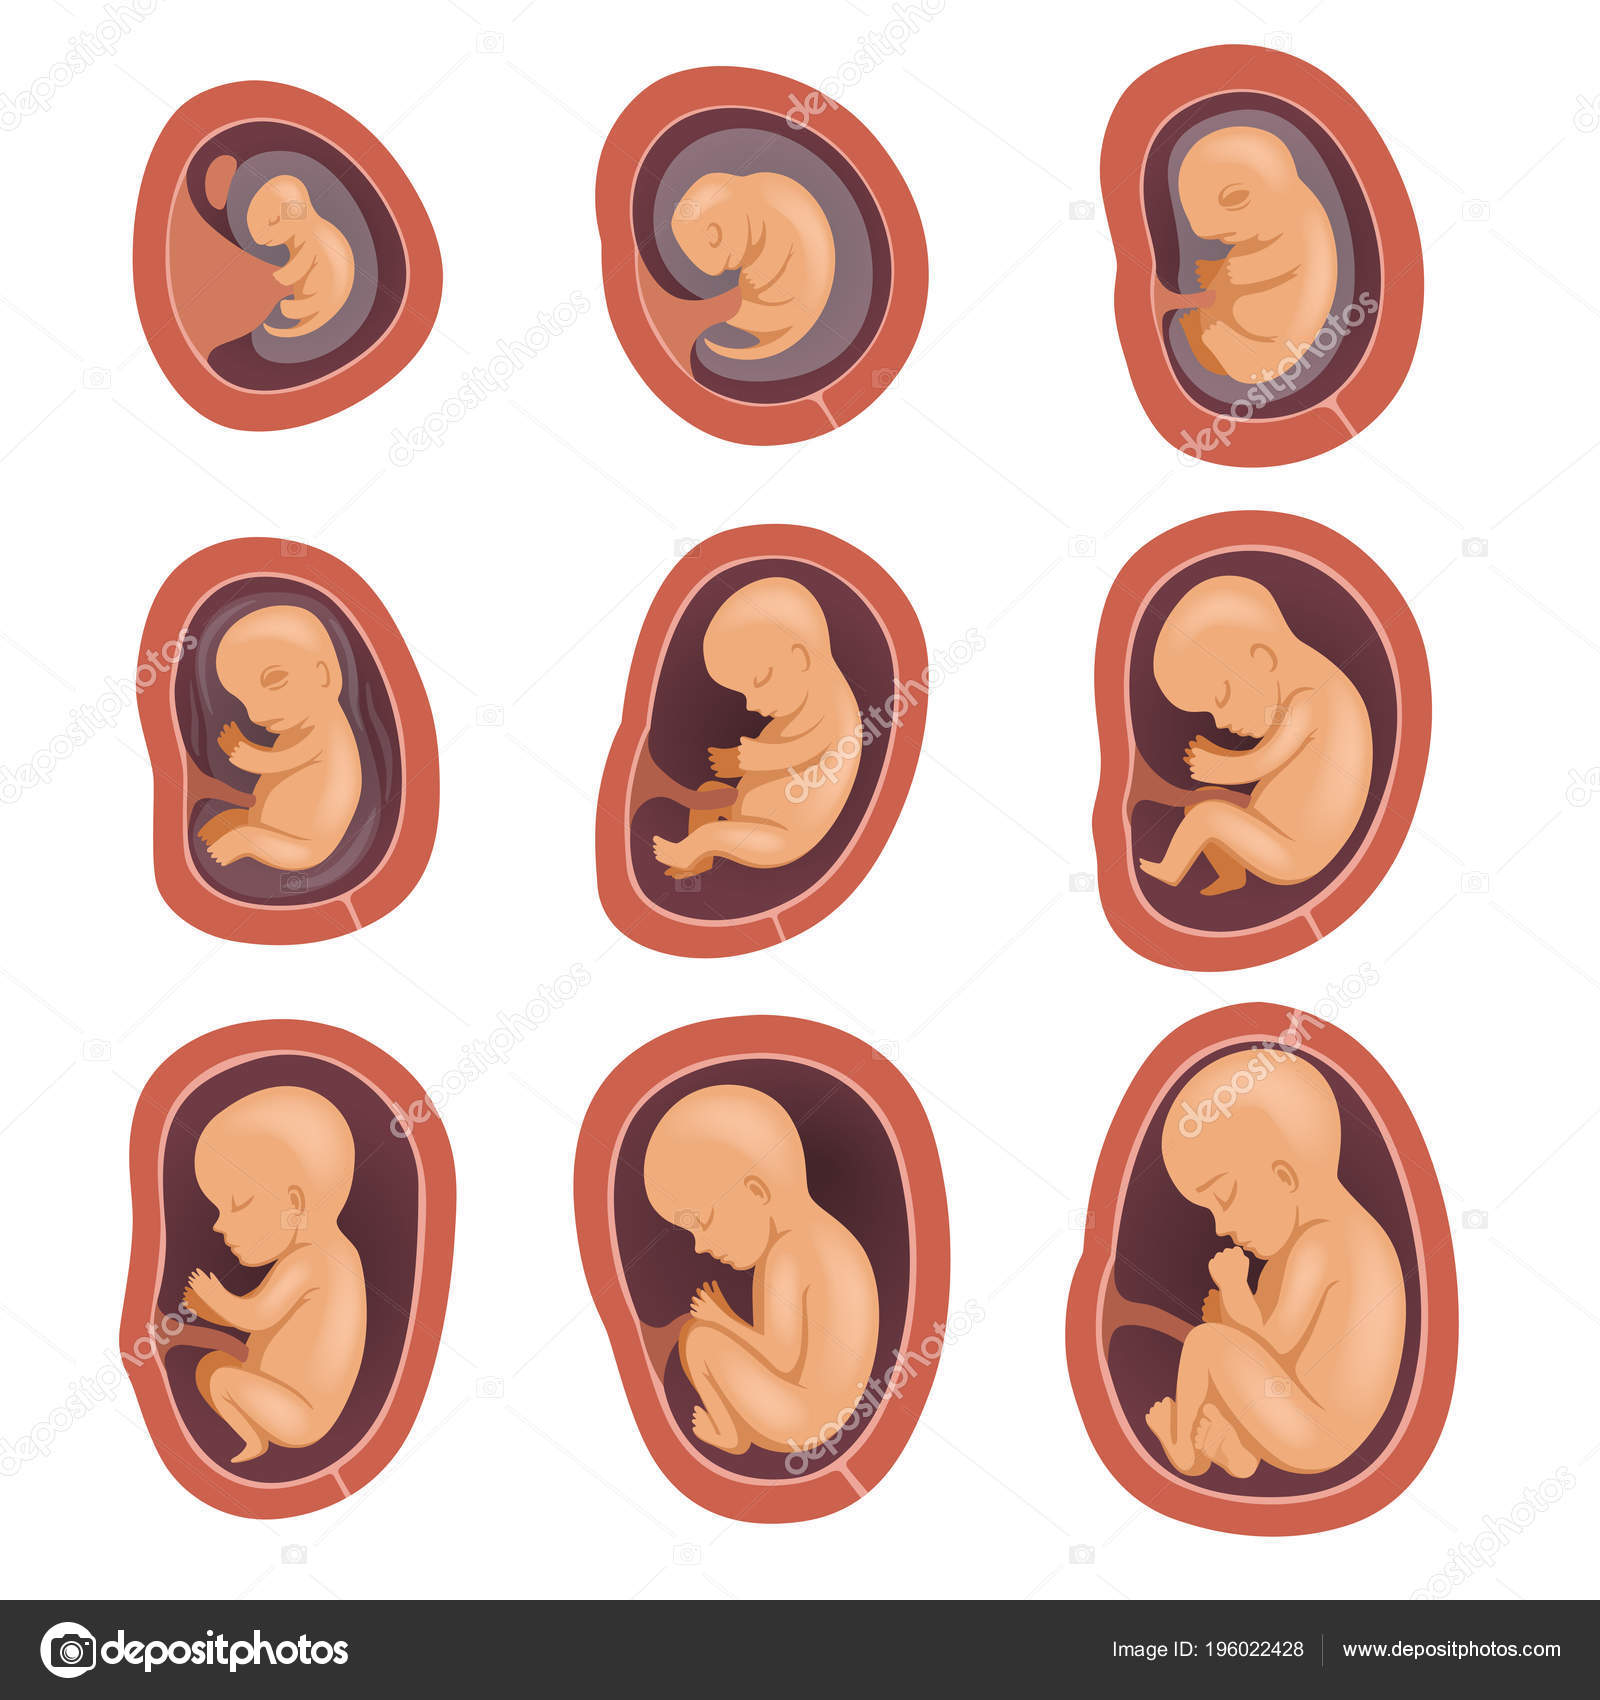

Фотография Плода В Животе

Фотография Плода В Животе 113 фотографий